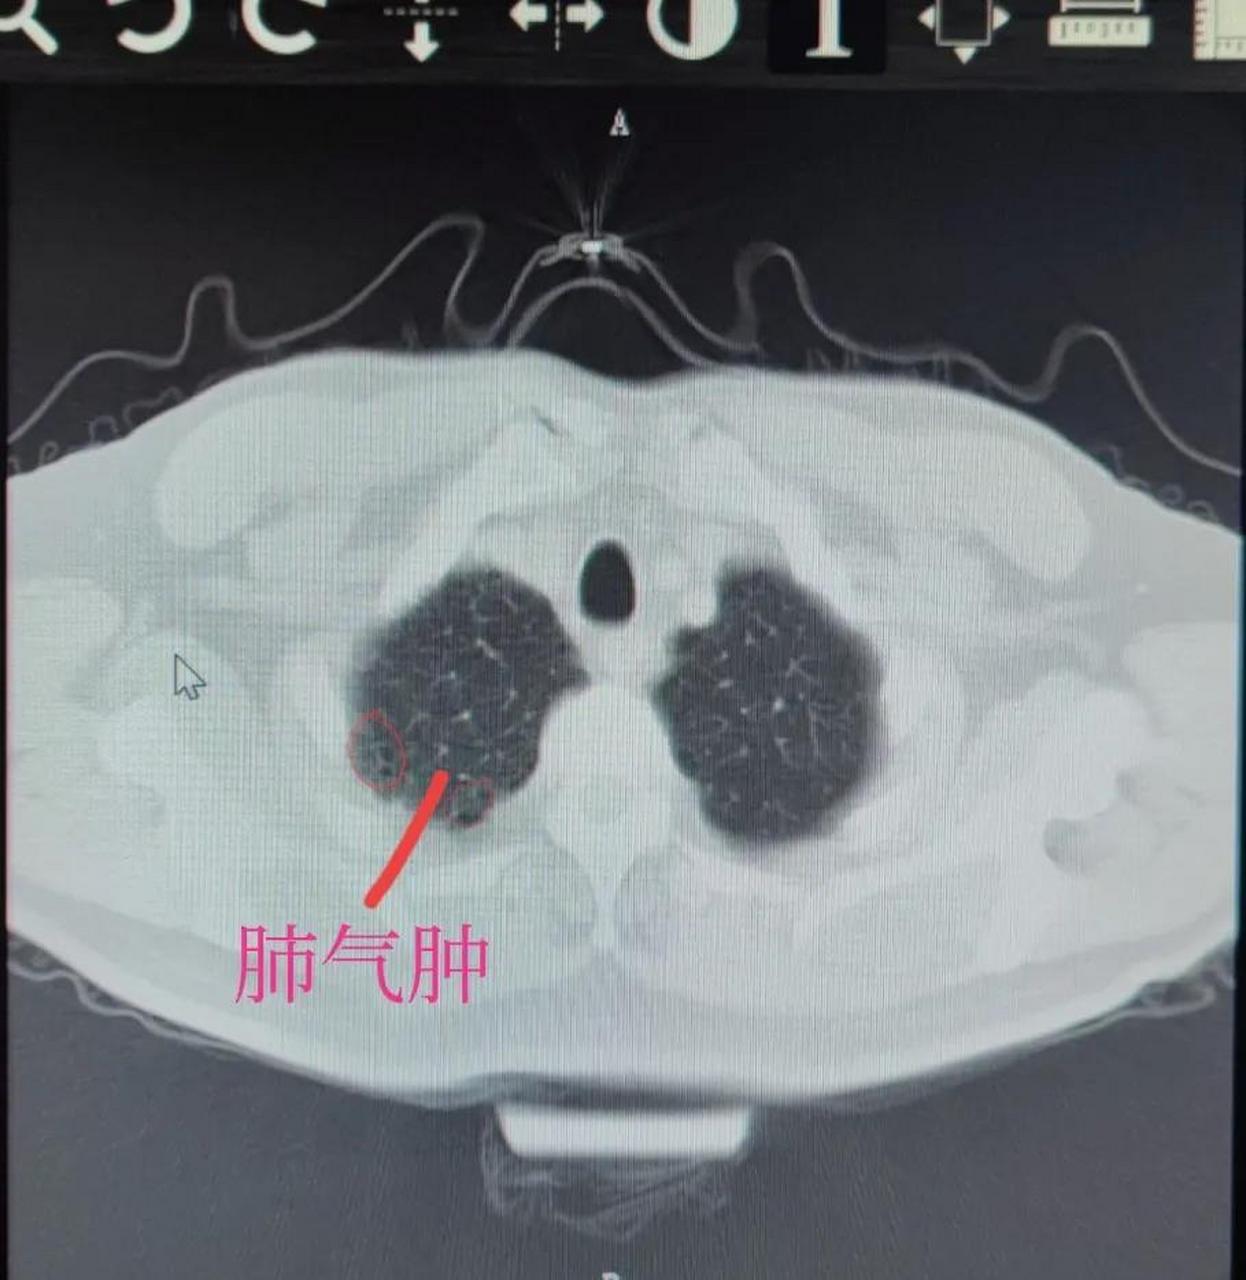

肺气肿ct分型

烟龄40多年,每天不到一包,不咳不喘,极轻度的慢支肺气肿患者的肺ct#给